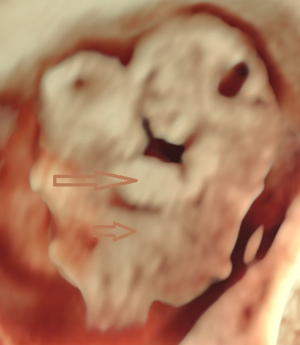

Chief complaint: a 27-year-old gravida presented for routine prenatal ultrasonographic evaluation. Early first-trimester ultrasound surveillance (6 weeks) revealed unremarkable fetal development. The patient denied any pregnancy-associated discomfort at this stage. History: bilateral salpingectomy performed. Personal and family history: the patient had no significant family or genetic history. Physical examination revealed no remarkable findings. All laboratory parameters fell within established normal limits. The patient used ART due to tubal factors. On 16 June 2024, the patient underwent a frozen-thawed blastocyst transfer. The two-dimensional (2D) ultrasound examination at 6 weeks of pregnancy showed a gestational sac in the uterine cavity, with a yolk sac inside and a 0.52 cm-long fetal bud close to the yolk sac, which showed a faint primitive heart tube pulsation. Ultrasound examination at 8 weeks of pregnancy showed a gestational sac in the uterine cavity, with one yolk sac, an amniotic sac, and two fetuses in the gestational sac. One fetus had a crown-rump length of 2.03 cm, and the other fetus had a crown-rump length of 1.88 cm. Both fetuses were consistent with an 8-week pregnancy. Both fetuses demonstrated complete thoracic ectopia cordis with anterior protrusion and cardiac fusion. The sagittal section showed that the two fetuses had a “ball-holding” sign, with a common heartbeat of 169 bpm (Figure 1). The organs above the umbilical part of the two fetuses were connected and protruded towards the front of the abdomen, with a cover on the surface. The cross-section of the chest showed that the two fetuses showed a “dumbbell” sign (Figure 2). The umbilical cords of the two fetuses were fused into a thick umbilical cord, and the entrance end of the umbilical cord abdominal wall was inserted into the fusion of the umbilical cord. The distal end of the umbilical cord was bifurcated and inserted into the placental parenchyma, respectively. Three-dimensional (3D) ultrasound surface imaging intuitively showed the relative positional relationship between the two fetuses and the exposure of the conjoined twins to the heart that fused each other on the outside of the chest cavity (Figure 3). Due to the early gestational week, the anterior diaphragmatic midline of the two fetuses was unclear. The ultrasound machine used in this case was a GE Voluson E10 (GE Healthcare, Chicago, IL, USA), with a RIC5-9-D probe. Figures 4,5 show normal fetus control images at the same gestational age.

With the widespread application of high-resolution transvaginal ultrasound, visualization of early pregnancy has become possible. The accuracy of assessing the risk of fetal chromosomal abnormalities through early pregnancy ultrasound combined with biochemical markers has improved, leading to the diagnosis of more fetal abnormalities in the early stages of pregnancy. A study indicated that ultrasound diagnosis of conjoined twins typically occurs between 11 and 13 weeks and 6 days. Screening at this stage can detect the most severe fetal malformations (8). There are reports that high-resolution ultrasound has advanced the diagnosis of conjoined twins to 7 weeks of gestation. However, due to the early gestational age, it is difficult to precisely determine the specific type of connection between the twins, and color Doppler ultrasound is typically required to assist in diagnosing the presence of conjoined twins (9). Fetal development is a process, and it can only be detected by ultrasound once it has reached a distinguishable gestational age. When fetal activity increases, around 8 weeks of gestation, it becomes easier to distinguish between monochorionic twins and conjoined twins (10). The patient underwent an ultrasound examination at 6 weeks of gestation, during which only a small, short, line-like embryonic bud and weak fetal heartbeat were observed. During the ultrasound examination at 8 weeks of gestation, we discovered that the two fetuses were embracing a “spherical” structure. The sagittal section revealed the “ball-holding” sign, and the transverse section showed a notch at the junction of the thoracic and abdominal walls, presenting the “dumbbell” sign. These two signs are specific to thoracoabdominal conjoined twins, with both fetuses affected by Cantrell’s pentalogy. Transvaginal 2D and 3D ultrasound provides direct evidence for the early identification of a special type of conjoined twins and advances the diagnostic gestational age to 8 weeks. Through transvaginal 2D ultrasound, the issue was identified, followed by adjusting the probe direction and angle to locate the specific connection site of the conjoined twins and determine the type of connection. The multiplanar views of 3D ultrasound provide additional detailed information. Adjusting the direction of light incidence, rotating the probe at multiple angles, and adjusting the 3D image, combined with surface imaging mode, yields more detailed features. The combination of 2D and 3D ultrasound provides more information than 2D ultrasound alone, offering more intuitive images, particularly suitable for fetuses with abnormal external features. A study has confirmed the role of 3D ultrasound in diagnosing prenatal abnormalities, which is consistent with our findings (11).

In summary, conjoined twins with bilateral Cantrell’s pentalogy likely represent the most severe phenotypic manifestation with the poorest prognosis. The characteristic “ball-holding” and “dumbbell” signs on ultrasonography serve as pathognomonic indicators of this condition in monochorionic monoamniotic twins. Early recognition of these sonographic markers is critical for timely diagnosis and management.